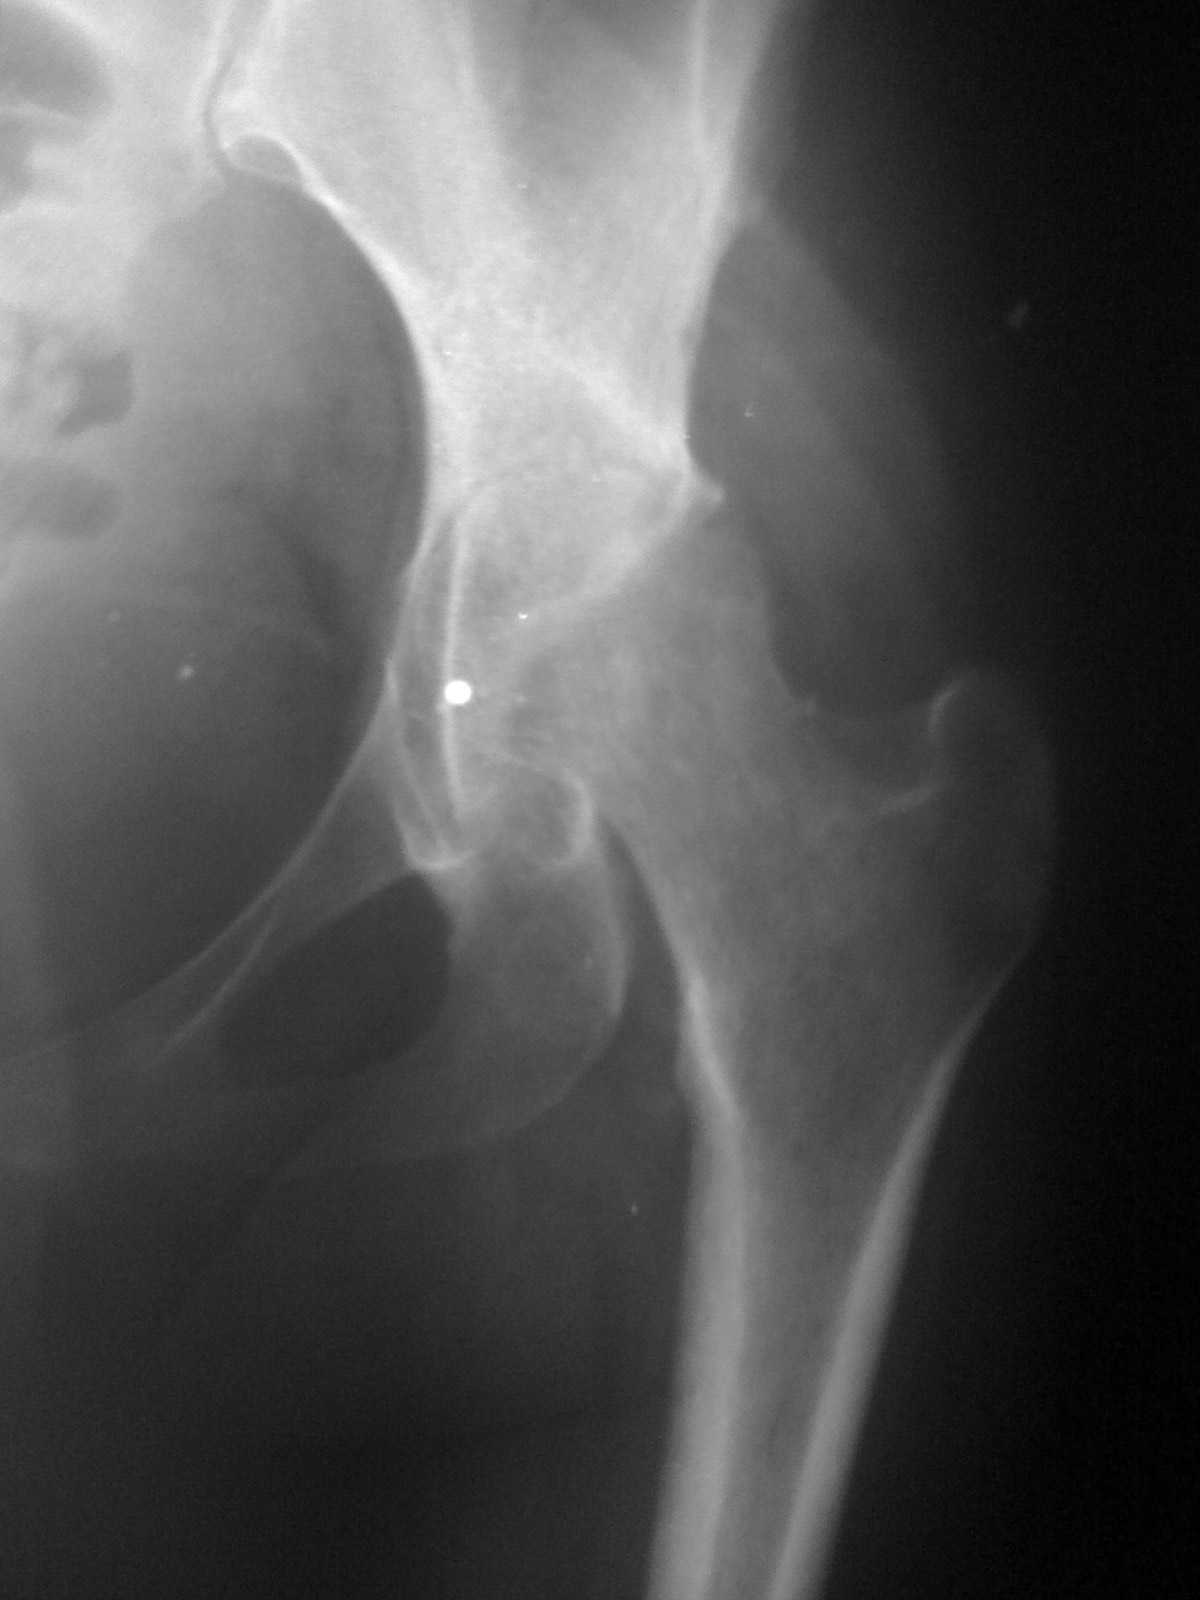

Коллеги! Пациентки 27 лет. Впервые обратилась 6 мес.назад после родов расхождение лонного

сочленения, проведена консервативно. Через 3 мес.повторное обращение по поводу болей в т\б

суставе.Ходит с костылями, отведение, приведение в суставе в пределах 10*.Укорочение

н\конечности на 3,0см.Непонятен механизм развития данной ситуации и какой метод лечения

выбрать. Если протез то какой?